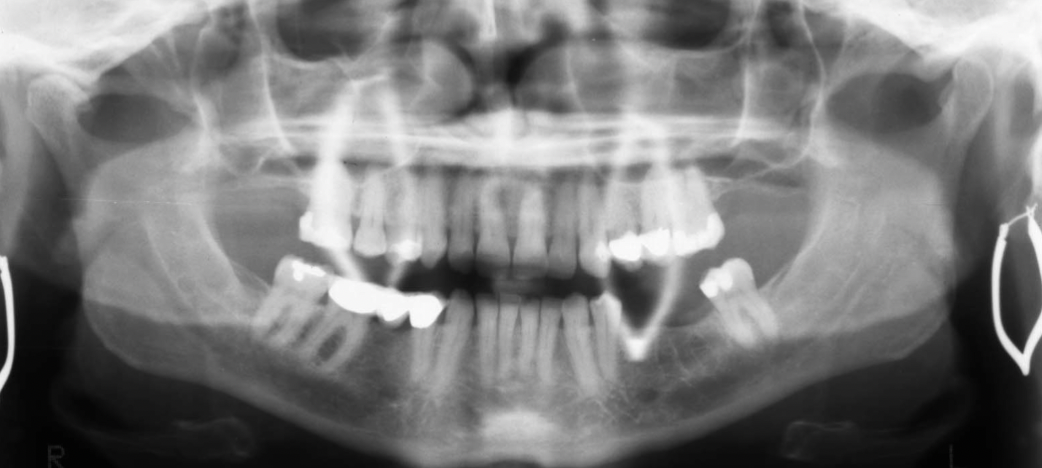

What are the errors in this radiographs? What is the cause of these errors?

A

1. anterior teeth widened & blurred

2. inferior tubercles and meati spread across maxillary sinuses

3. condyles are close to or cut off side image

Cause: Pt too far back